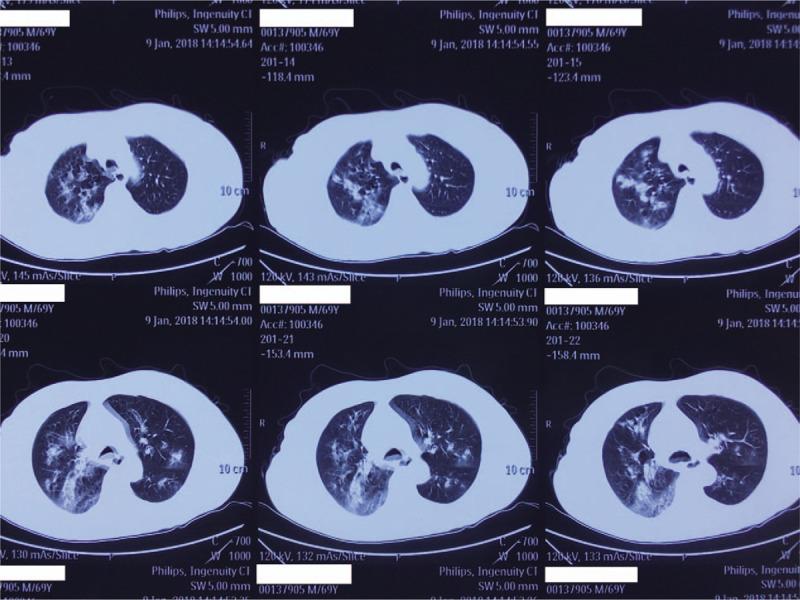

PATIENT CONCERNS

A 68-year-old male with no concerning medical history had developed a fever that reached 39.0°C, a productive cough that was sustained for 5 days, and hypodynamia. He was treated with azithromycin and alexipyretic in a nearby clinic for 2 days in which the symptoms were alleviated. However, 1 day later, the symptoms worsened, and he was taken to a local Chinese medicine hospital for traditional medicine treatment. However, his clinical condition deteriorated rapidly, and he then developed dyspnea and hemoptysis.

DIAGNOSIS

CA-MRSA pneumonia and septic shock. The sputum culture showed MRSA. Polymerase chain reaction of MRSA isolates was positive for PVL genes.